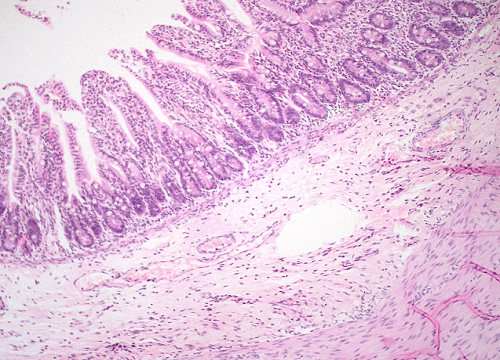

Question 14

Question

Label this image

Image:

a8a6dedd-9635-4a50-b0b7-ae26628932ea (image/png)

Answer

Small Intestines